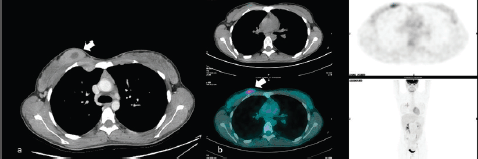

MS can also be found fortuitously during CT or PET examination in oncologic patients ([14–16]; Figure 8).

The typical appearance is of an irregular breast mass with inhomogeneous contrast enhancement and glucose uptake. On occasion, patients with MS of the breast can present other soft tissue localisation, such as the kidney (Figure 9).The histopathological diagnosis is challenging especially for the difficulties encountered distinguishing MS from lymphoma (Figures 10–12).

Figure 8. A 50-year-old patient presenting a right unilateral, incidental finding of breast mass subsequently demonstrated to be a MS. (a): Irregular breast mass on the computed tomography exam, showing inhomogeneous contrast enhancement (arrow). (b):The abnormal glucose uptake in PET examination (arrow).

Figure 9. Same patient of Figure 8, showing irregular contrast-enhancing soft tissue mass (arrow), resulting in the localisation of MS.